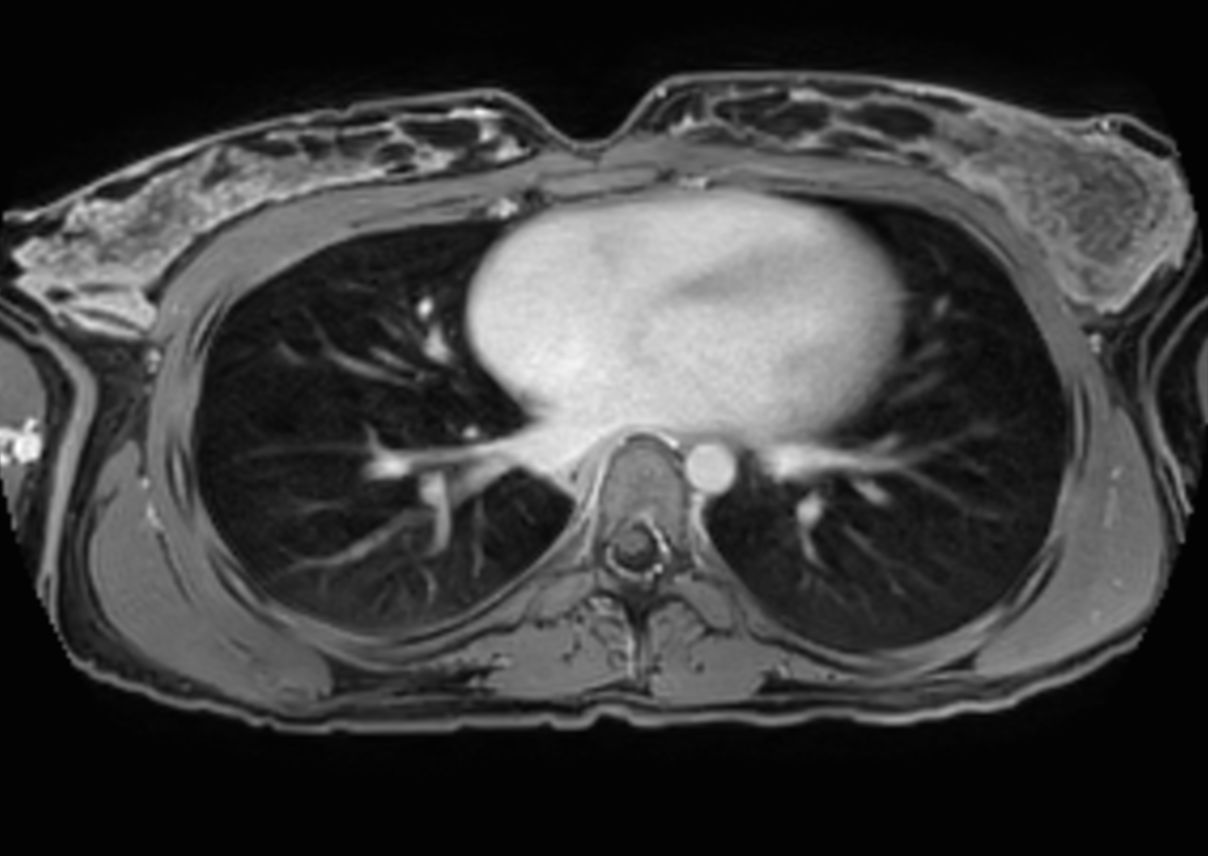

T2w TSE - MultiVane XD